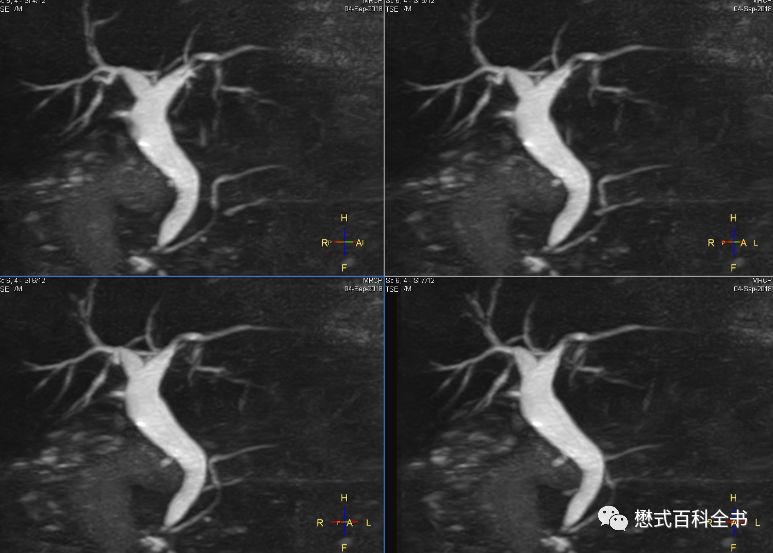

图21:3D MRCP扫描

如图,3D MRCP扫描,容积采集后,然后做MIP(最大信号强度投影重建)。

3D MRCP优点是:信噪比高,可以出薄层图像,而且可以通过图像后处理MIP形成胆管树形结构图,这种图临床医生非常喜欢看,对胆管系统整体结构显示清晰。

但是,3D MRCP也有致命的缺点,如图,如果没有经验的影像医生或者临床医生只看重建的MIP图,而不看原始的薄层图像,则容易出现假阴性(由于最大信号强度投影的图像后处理算法关系,有可能把本来的充盈缺损,显示结石的给遮掩了)。本来有结石的,结果做了MIP后,无法显示充盈缺损了。另外,3D MRCP序列扫描时间也长。